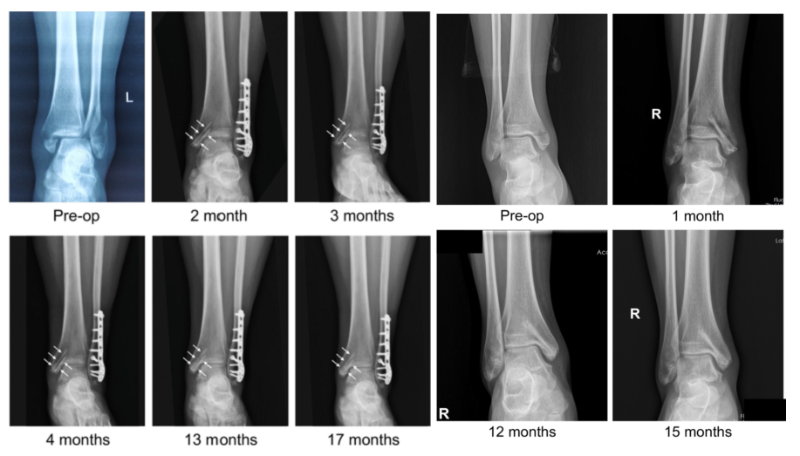

近日,國際骨科臨床轉化期刊《Journal of Orthopaedic Translation》在線發表了由上海交大戴尅戎院士、郝永強教授團隊和丁文江院士、袁廣銀教授團隊合作發表的可降解鎂合金骨釘1-2年的臨床試驗觀察結果,所有患者術后內踝骨折愈合,功能恢復。研究證實了可降解鎂合金螺釘治療內踝骨折的臨床療效及其生物安全性,為全降解鎂合金植入物等高端醫療器械進一步的臨床推廣應用奠定了堅實基礎,相關成果以“Effectiveness and safety of biodegradable Mg-Nd-Zn-Zr alloy screws for the treatment of medial malleolar fractures”為題在線發表于Journal of Orthopaedic Translation,27 (2021) 96–100。這是國內首個可降解醫用鎂合金臨床試驗的公開報道,也是國際首款含有功能涂層的可降解鎂合金骨釘的臨床試驗結果的公開報道,具有里程碑意義。

目前臨床上廣泛使用的骨折內固定器械大多由不可降解金屬如不銹鋼或鈦合金等制備而成,存在彈性模量過高,臨床上易引起應力遮擋效應而影響骨愈合,同時因為不降解植入后需二次手術取出等缺點。鎂合金材料因彈性模量與皮質骨相近,可消除應力遮擋效應,同時可體內降解并被人體安全吸收代謝而避免了二次手術等優點,被譽為“新一代革命性的金屬生物材料”。

針對鎂合金材料體內降解釋放氫氣的現象,袁廣銀教授帶領課題組歷經數年攻關研發出了具有生物活性、本身可以降解、同時可以抑制基體過快降解的涂層專利技術,成功解決了鎂合金材料在體內降解過快產生氫氣集聚的不良現象(ACS Applied Materials Interfaces 2014, Mater Sci Eng C 2018, Biomaterials 2020)。通過從材料基體和功能涂層兩方面協同調控其降解行為,在國際上率先實現了醫用鎂合金骨內植入器械的均勻可控降解。